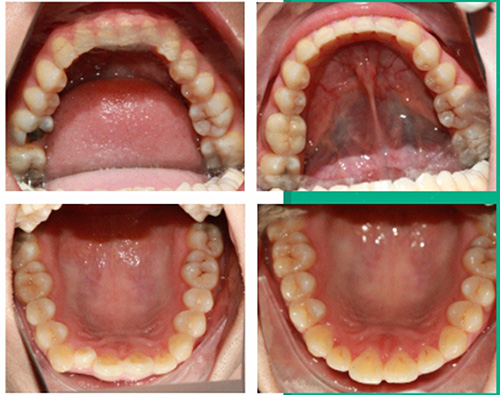

而案例中的患者虽然牙列并没有拥挤的情况,但是有些轻微的前牙反牙合问题,但是幸好反覆盖的面积并不大,属于齿性的地包天问题,所以通过正畸就能起到改善的效果。

通过矫正后的效果能够看到,前牙反牙合的问题已经得到改善,矫正后的效果还是非常明显的。